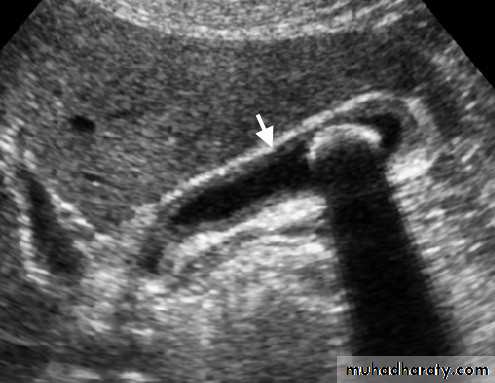

Signs of acute appendicitis on US:

• Thickened edematous appendix [diameter > 6 mm].

• Non-compressible blind ending tubular structure.• Appendicolith.

• Local free peritoneal fluid.

• Sentinel dilated bowel loop.

• Complication: abscess, inflammatory mass.

Limitations of US:

• The normal appendix is often not visualized• Retrocecal appendicitis may be obscured.

• The negative predictive value of a negative US examination is not as high as for CT.